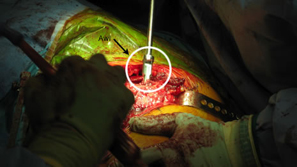

| Removal of Hardware (two screws) |

Level and orientation of osteotomy is critical to the entire surgical case |

| Femoral canal preparation is begun with an opening into the femur with a starting awl, followed by a circular box chisel. |

Cup orientation and preparation is challenging and care should be taken not to penetrate the medial wall. Proper cup placement is difficult do to loss of bony landmarks. Hip abductors will be weak and joint instability is a significant concern. Lateralization of the femoral component will aid in reducing forces across the hip joint potentially reducing limp and post-operative hip dislocation.